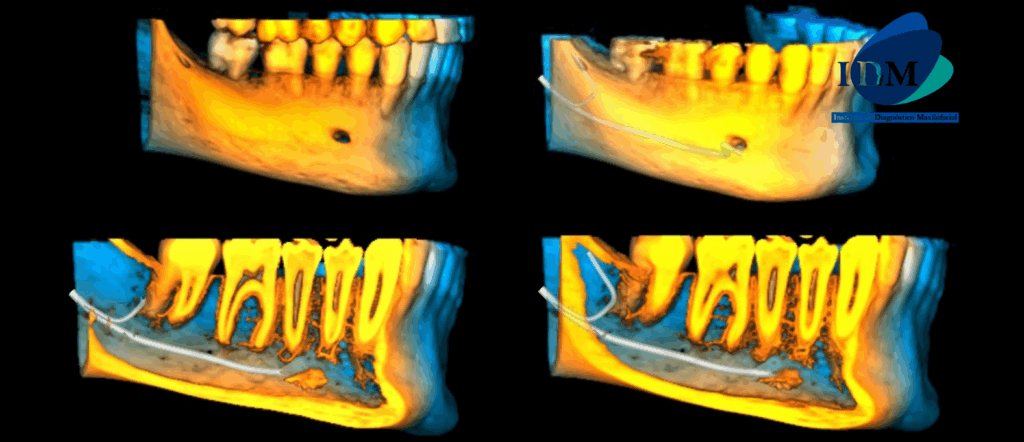

En las reconstrucciones 3D se representa de manera didáctica Bifurcación de conducto dentario inferior (Figura 4).

RECONSTRUCCIÓN 3D